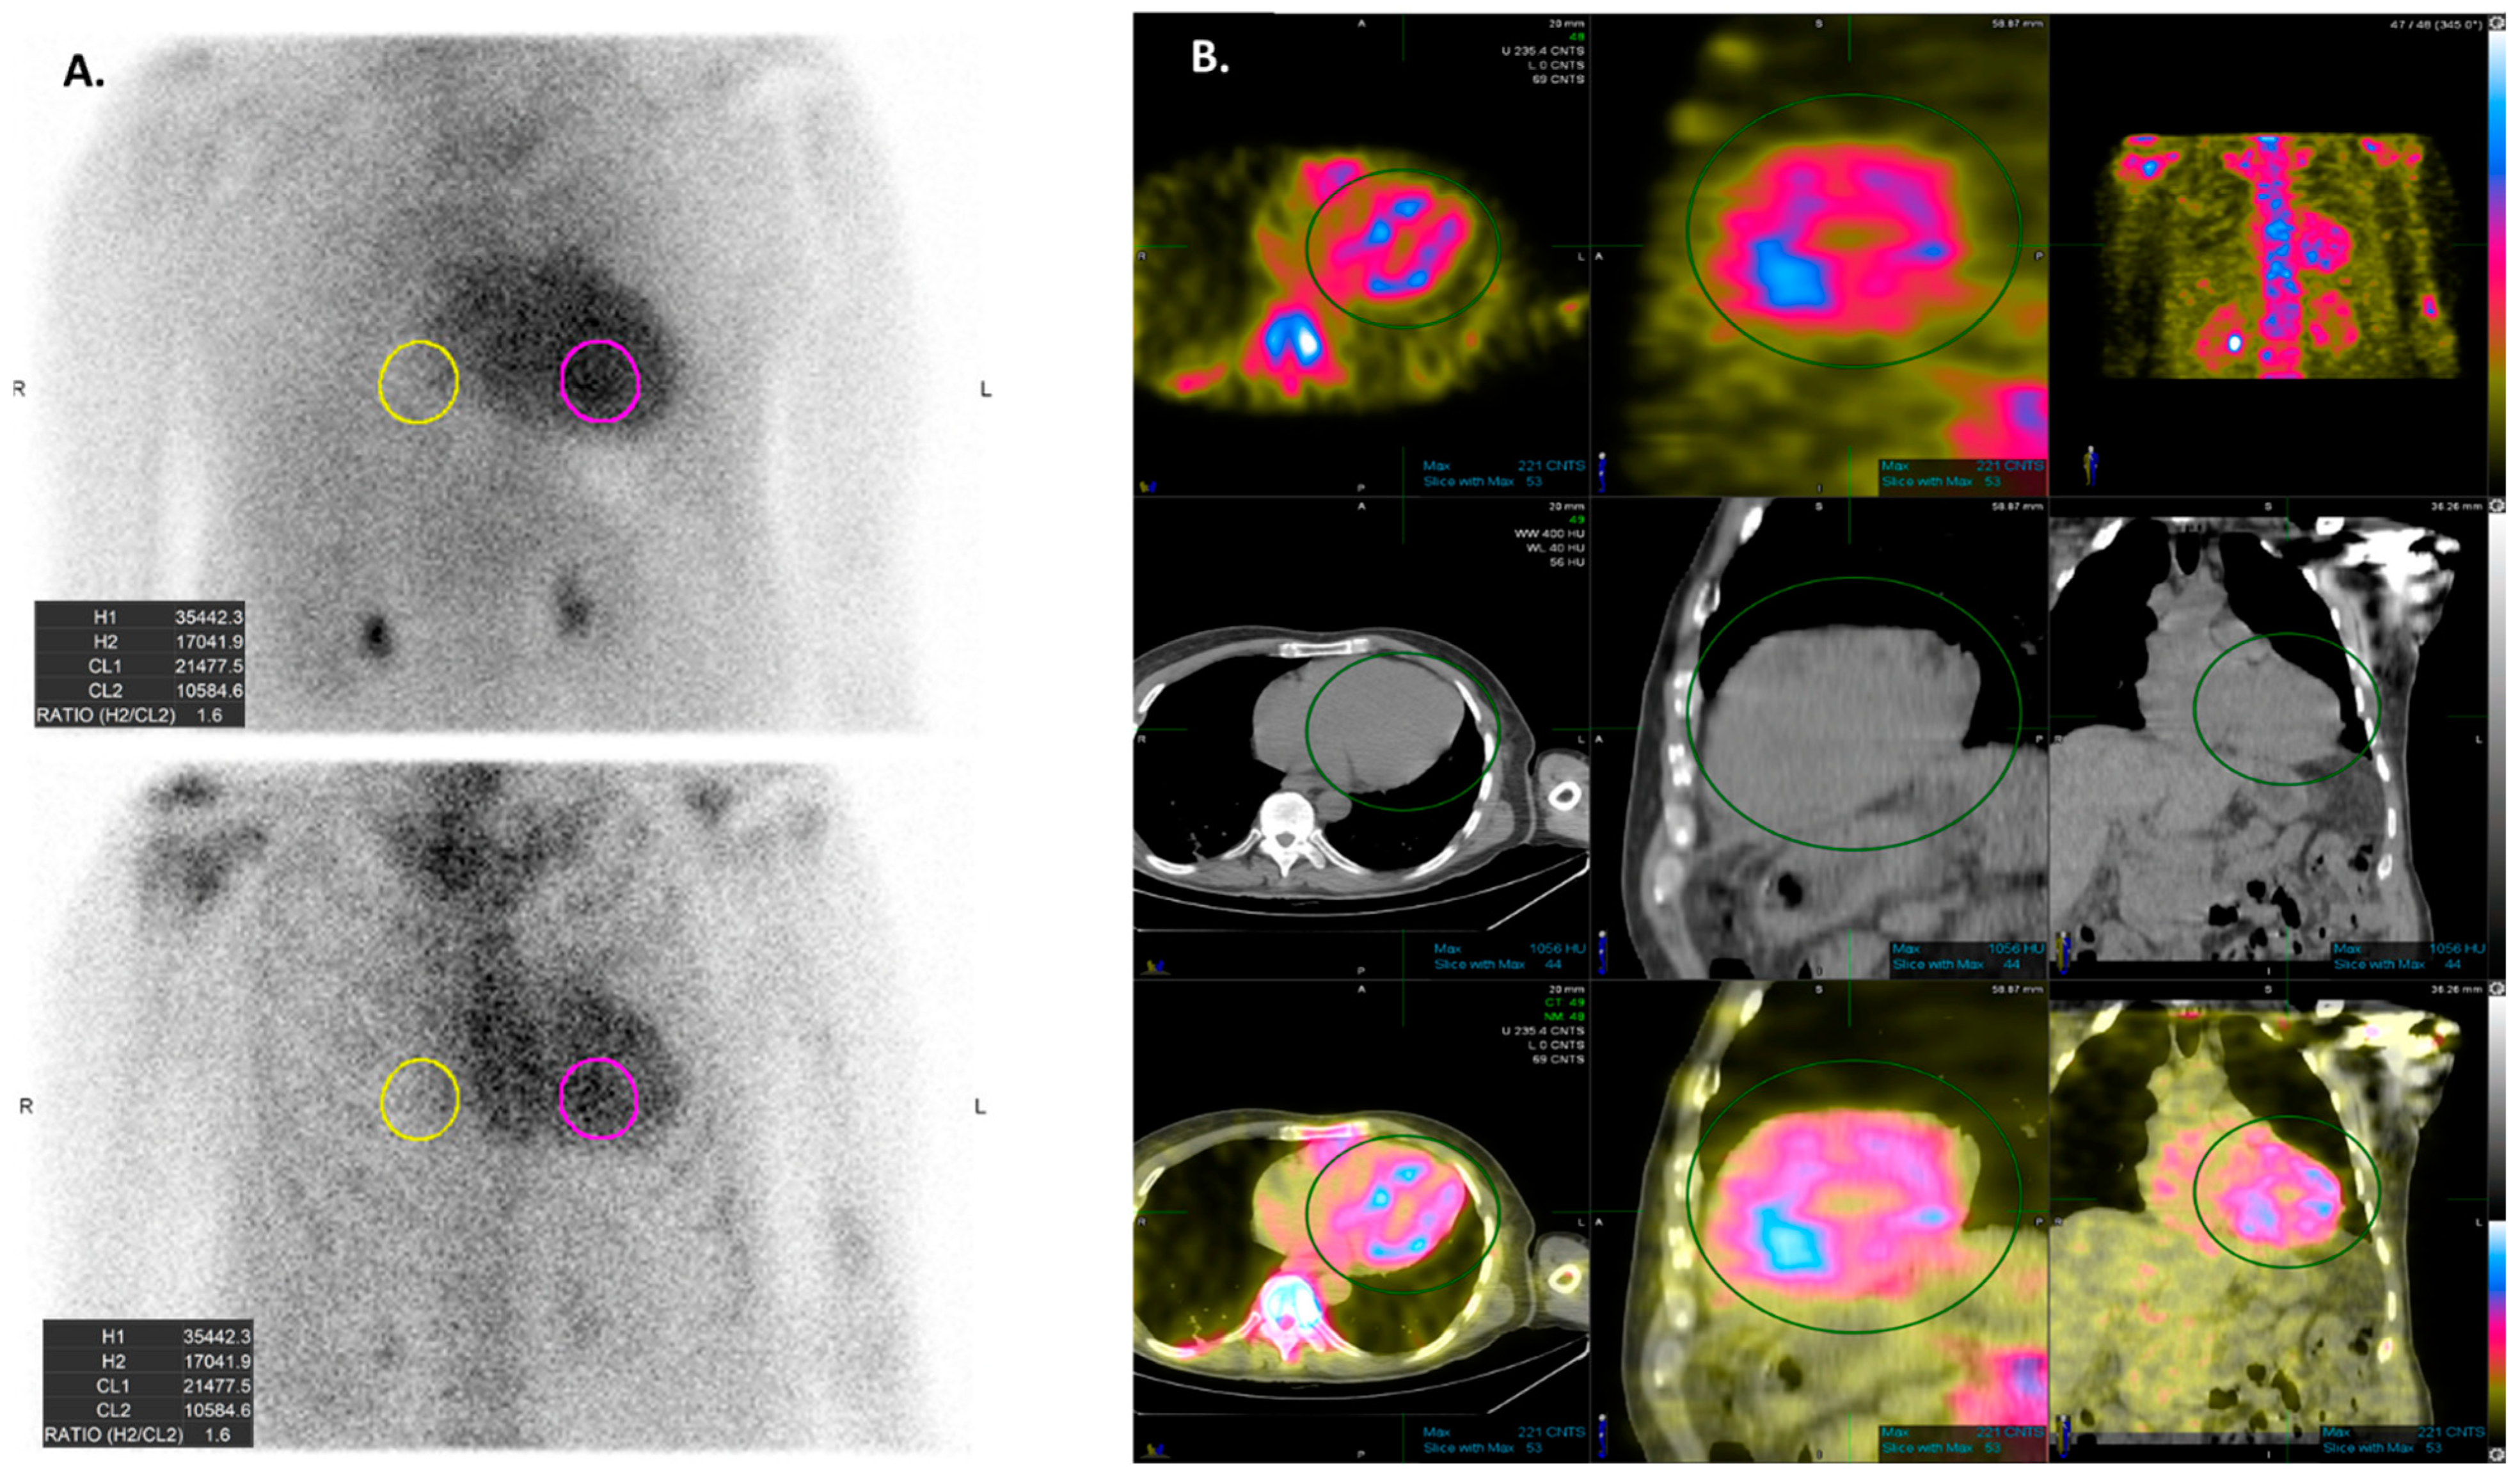

| Grade 0 | No cardiac uptake. |

| Grade 1 | Mild cardiac uptake, less than that in ribs. |

| Garde 2 | Moderate cardiac uptake is similar to that in ribs, but uptake in ribs remains clearly visible. |

| Garde 3 | Intense cardiac uptake greater than that in ribs with weak or no signal evident in ribs. |